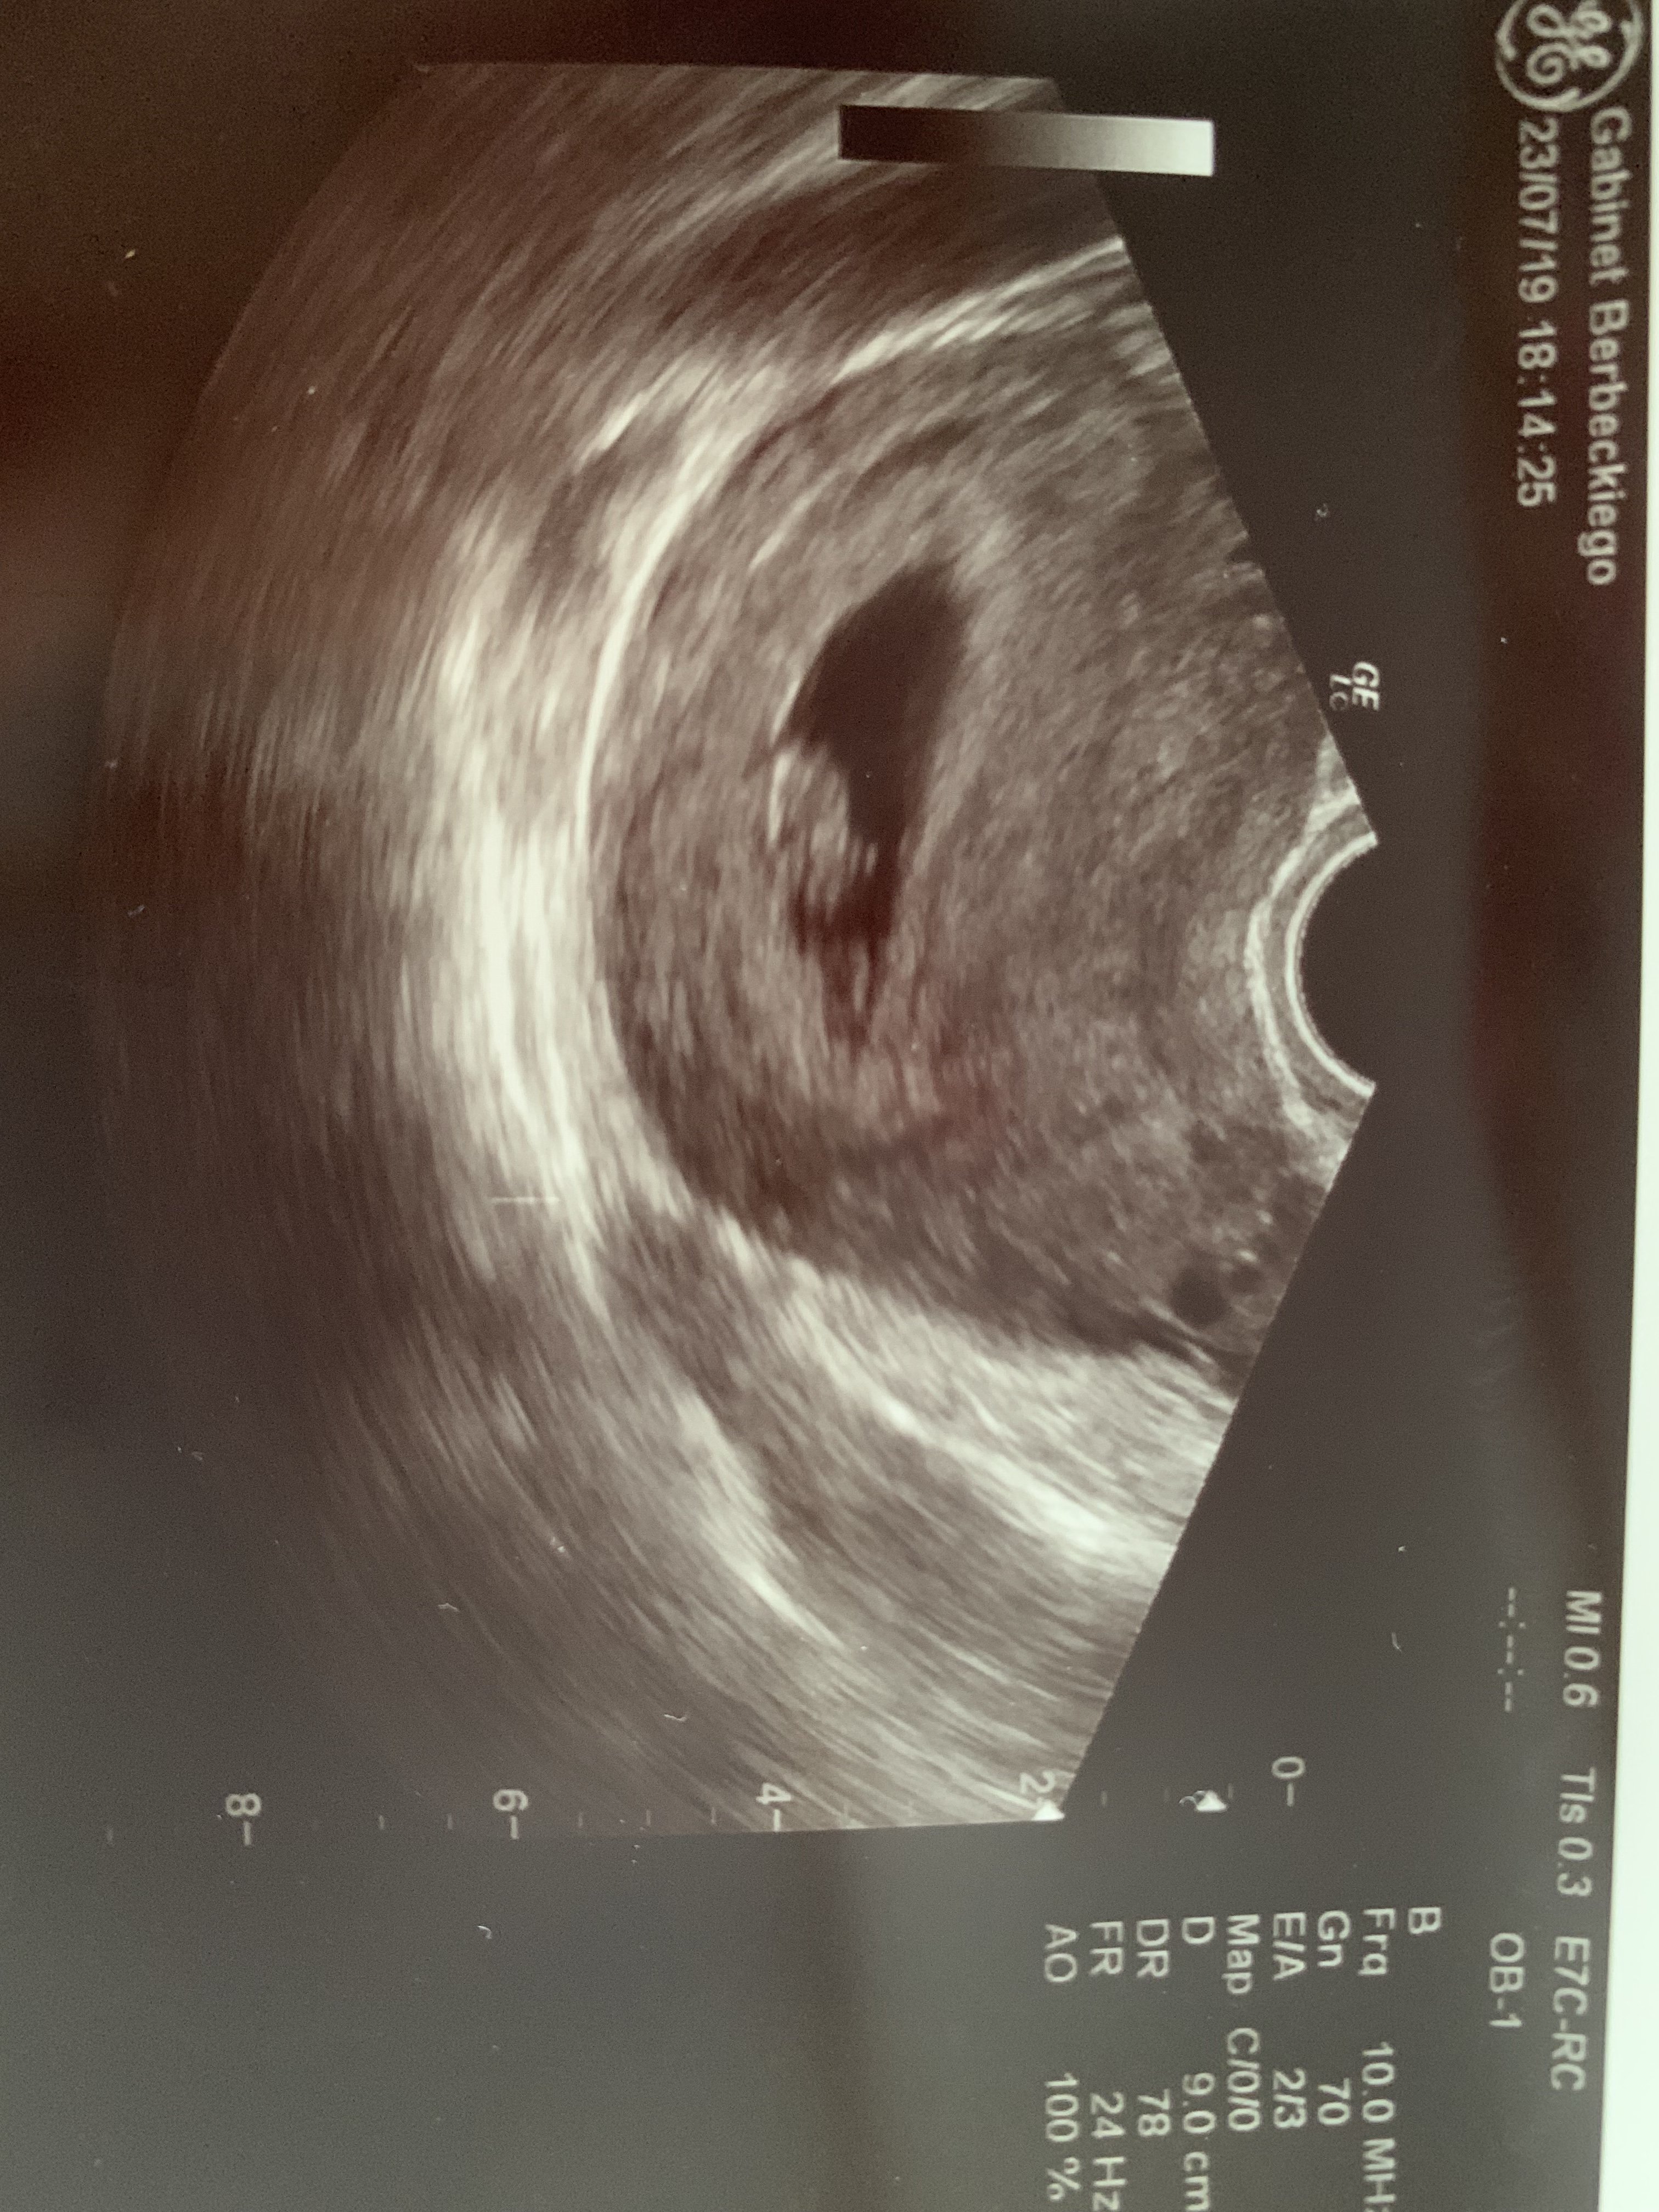

Ja już po I jest super ;) mój Kropek ma 15mm I bije serduszko ;) wiek ciąży według usg to 8+3 jestem dużo spokojniejsza super ;) niby powiedział że najwięcej zagrożeń do 9 tygodnia ale już jestem zrelaksowana, czyli te bóle itd to przez to że pracuje fizycznie, ale już widziałam rączki i nóżki ;) wrzucę wam zdjęcie jak dopafne telefon męża. Bo ma zdjęcie on na telefonie.

Jestem szczęśliwa [emoji846] serduszko pięknie bije - puściła mi dosłownie na sekundę [emoji846] dzidzia ma 1cm, termin nadal na 7 marca. Kolejna wizyta 01.08 bo wyjeżdżamy na wczasy i pani doktor chce mnie mieć na oku [emoji846] dostałam tez luteinę profilaktycznie [emoji846]